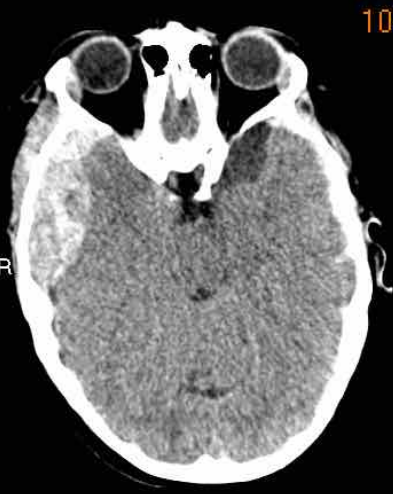

下图显示硬膜下血肿。

注意血肿有高密度区和等密度区。

这可以在超急性出血中看到,但也可以在再出血中看到。

中线结构移位,脑脊液血流受阻,导致右侧脑室颞角扩张(箭头)。

急性硬膜下血肿为高密度(凝血),亚急性血肿为等密度,慢性硬膜下血肿表现为低密度(同脑脊液)。